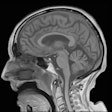

fMRI software falls short of expectations